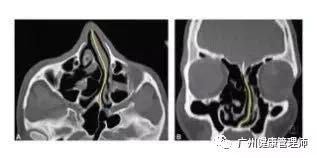

CT顯示扭曲的鼻中隔(黃線)使經鼻氣道不暢,多源于面部撞擊傷。